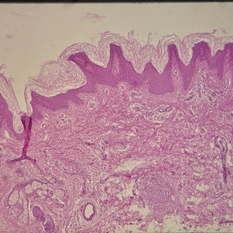

Histopathology of Linear Sebaceous Nevus Syndrome

Histopathology of Linear Sebaceous Nevus Syndrome

Feb 20 2015 by H. Michael Lambert, MD

Histopathology of linear sebaceous nevus syndrome.

Condition/keywords: histopathology, linear nevus sebaceous syndrome

Histopathology of Linear Sebaceous Nevus Syndrome

Histopathology of Linear Sebaceous Nevus Syndrome

Feb 20 2015 by H. Michael Lambert, MD

Histopathology of linear sebaceous nevus syndrome.

Condition/keywords: histopathology, linear nevus sebaceous syndrome

Histopathology of Linear Sebaceous Nevus Syndrome

Histopathology of Linear Sebaceous Nevus Syndrome

Feb 20 2015 by H. Michael Lambert, MD

Histopathology of linear sebaceous nevus syndrome.

Condition/keywords: histopathology, linear nevus sebaceous syndrome